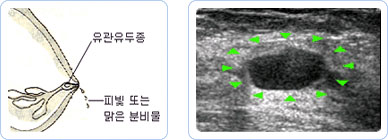

유관 유두종은 유관 안에 유두모양으로 생기는 양성종양으로써 여러 가지 증상을 나타내는 유방질환입니다. 1~3mm 정도의 작고 부드러우며 잘 부서지는 덩어리로서 3~4mm이상 커지지 않는 한 겉으로 만져서는 구별하기도 힘들고 혹이 만져져서 병원에 오는 경우도 매우 드뭅니다.

유관 유두종은 주로 분비물이 생겨 발견되는 경우가 많으며 물같이 맑거나 붉은 분비물이 유두의 한 구멍에서만 반복적으로 나옵니다.

주로 유두나 유륜 밑에 있는 유관에 생기며 유방촬영이나 초음파로는 잘 나타나지 않아 유방조영술로 진단이 이루어집니다.